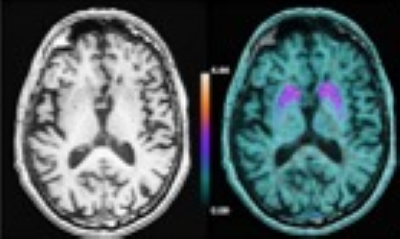

La DRF est au CEA le premier acteur de cette transition à la fois par ses recherches en sciences du vivant et par les instruments qu’elle développe. En terme de santé numérique, le CEA est leader en imagerie cérébrale avec des installations phare comme la TEP-IRM, l’IRM très haut champ ou la MEG. L’enjeu de santé est le développement de diagnostics et les études des maladies cérébrales. La DRF est pionnière des approches « omiques » avec la génomique et la métabolomique. En recherche, l'enjeu aujourd’hui est de passer à une approche multi-omiques et de corréler cette masse de données multimodales à des pathologies et des indications thérapeutiques.